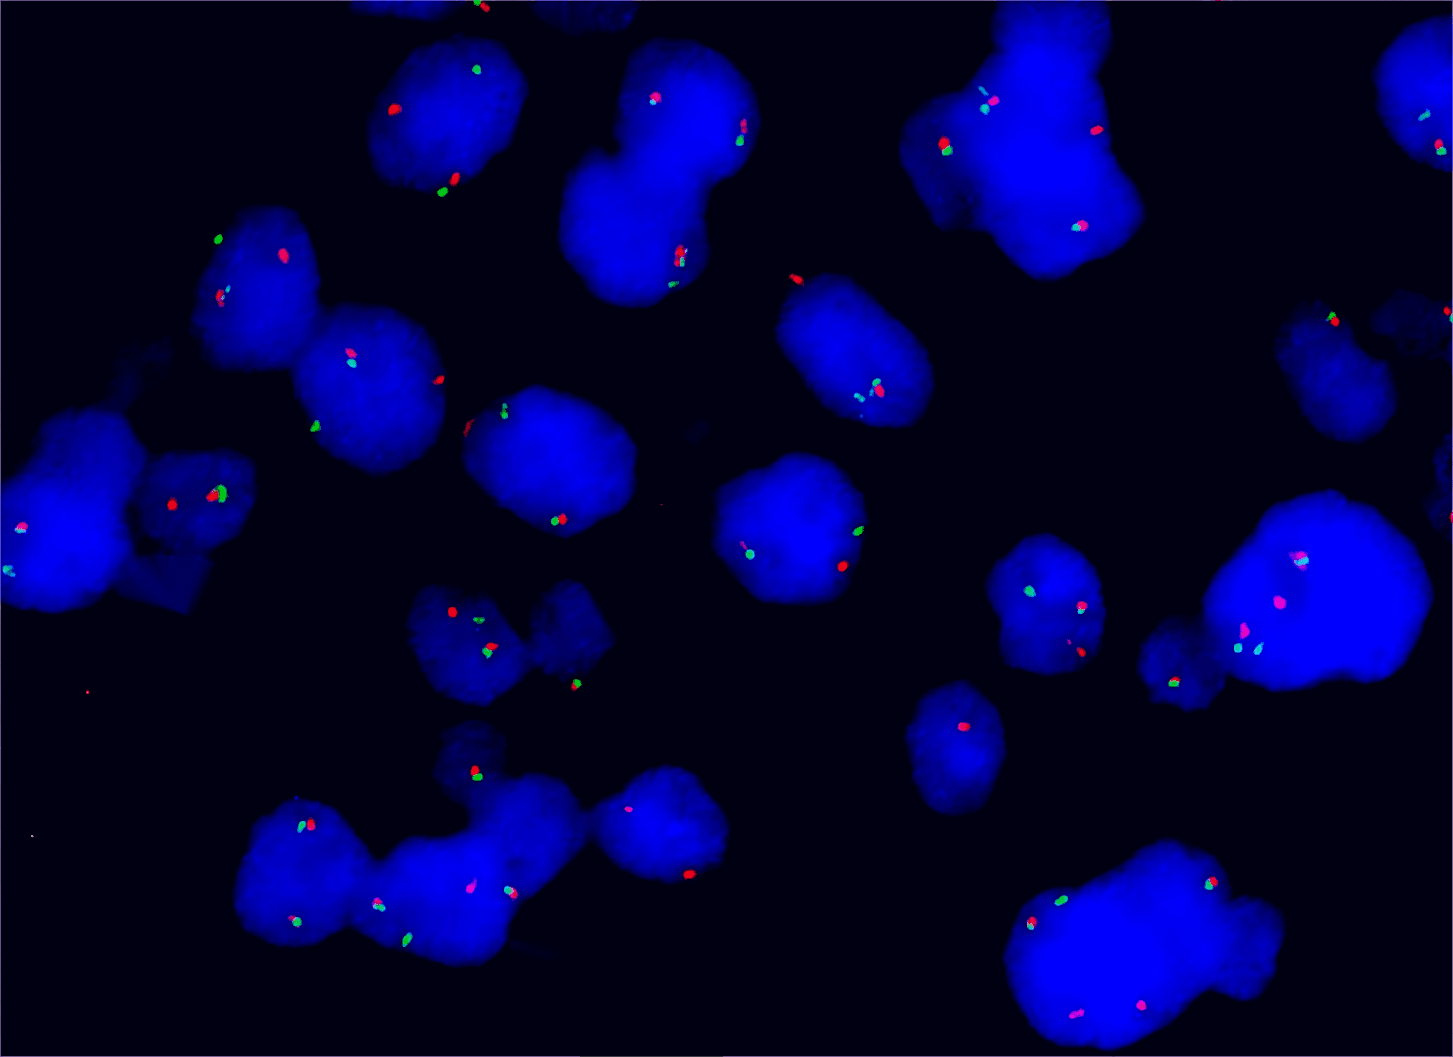

BCL6/MYC/IGH/[BCL2/IGH] gene probe reagent

BCL6/MYC/IGH/[BCL2/IGH] gene probe reagent

BCL2/IGH dual color probe

Description:

BCL2 gene (18q21.3) labeled as orange, with a length of 800 kb; IGH gene (14q32) labeled as green, with a length of 1580 kb.